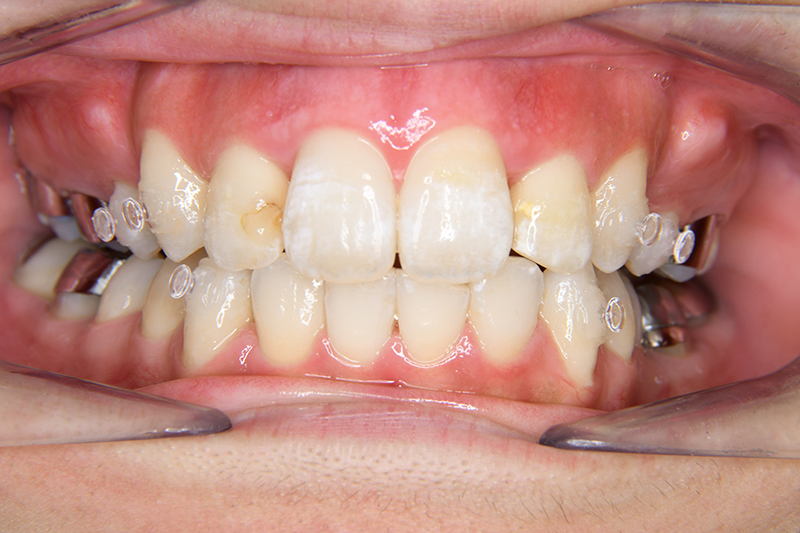

初診時

FP・IOP

主訴 出っ歯 診断名 アングルⅡ級2類

初診時年齢 24歳11ヵ月 性別 動的治療期間 20ヵ月

顔貌所見 正貌はほぼ対象。側貌はconvex type、著しい口唇閉鎖不全が認められた。

口腔内所見 over jet 11.5mm、over bite 5.5mm、右側臼歯関係Full ClassⅡ級、左側end onⅡ級、上顎顎歯列はテーパー型であり、上顎中切歯は押し出されるように大きく唇側傾斜していた。下顎前歯部は叢生を呈しており、左下5は歯冠長が短く半埋伏していた。